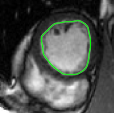

Figures 8 and 9 shows some sample tracking results of the proposed method and Medviso on full cardiac cycles of two different cases on both the LV dataset and the RV dataset. The ground truth (yellow) is superimposed when available. A summary of the results on the entire datasets is shown in Table I. The accuracy with respect to ground truth is measured using average perpendicular distance (APD) and dice metric (DM) for left ventricle, and Hausdorff distance (HD) and DM for the right ventricle. These metrics are chosen since they are the standard ones used on these datasets. Both qualitative and quantitative results show that our proposed method leads to more accurate segmentation of the ventricles and thus leads to less interaction than segmentation propagation schemes in than Medviso.

| initial | ventricle tracked (red - algorithm result, yellow - ground truth) | |||